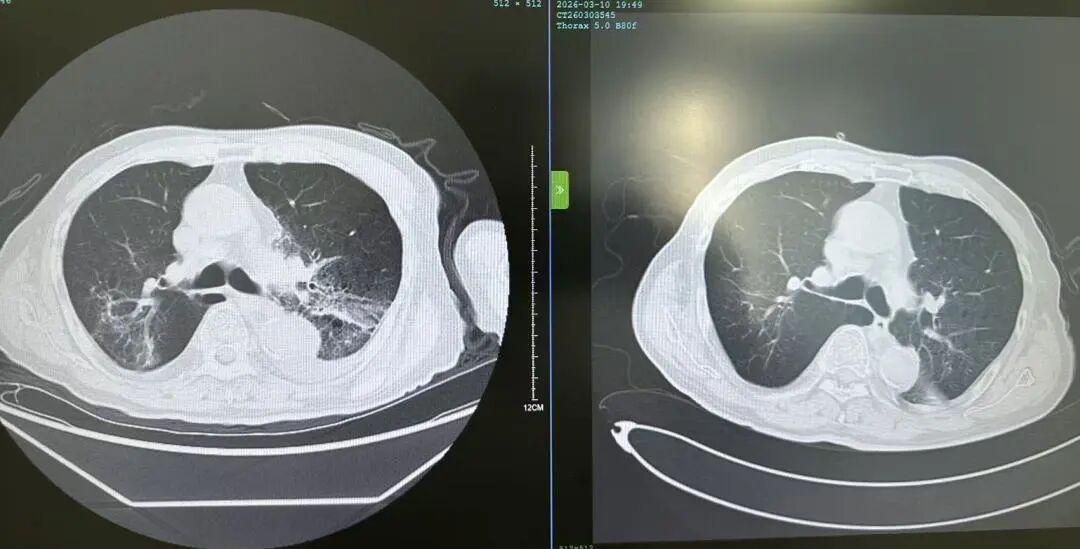

花鸟相伴本是生活雅趣,但鸟类羽毛碎屑、排泄物及粉尘中潜藏的有害物质,却可能悄然成为肺部健康的“隐形杀手”。这类疾病起病隐匿、症状不典型,极易被误诊或漏诊,严重时甚至可迅速进展为重症肺炎、呼吸衰竭,危及生命。近日,葫芦岛市第二人民医院呼吸与危重症医学科连续收治多例与接触鸟类密切相关的肺部疾病患者,为广大“养鸟一族”敲响警钟。 病例一:久咳不愈竟致呼吸衰竭 真凶竟是“养鸟过敏” 50岁的刘先生咳嗽、咳痰、气短两个月,严重时彻夜难眠,辗转求医无果,入院时已确诊I型呼吸衰竭。肺部影像学检查显示,双肺广泛存在磨玻璃影,局部已呈现“白肺”表现。此时,鉴别是感染性还是非感染性因素,成为诊断的关键。 ↑氧分压<60mmHg、二氧化碳氧分压正常、呼吸频率异常,呼吸衰竭 ↑相关检验项目正常,排除感染性因素 宋刚主任细致追问病史,发现其长期接触鸟类,结合支气管镜检查排除常见感染,最终明确诊断为外源性过敏性肺泡炎(过敏性肺炎),合并急性喘息性支气管炎。病因正是吸入鸟类羽毛及排泄物中的特异性蛋白过敏原,导致肺部过敏性炎症损伤。在脱离过敏原、接受经鼻高流量等规范治疗后,刘先生症状迅速缓解,顺利康复出院。 ↑左侧为治疗后肺部影像,右侧为治疗前肺部影像,肺炎明显减轻 病例二:高龄重症合并多重基础病 幕后黑手竟是鹦鹉热衣原体 86岁的杨大爷持续高热3天,体温达39℃,入院时已出现严重呼吸衰竭。更棘手的是,患者有20年再生障碍性贫血病史,白细胞、血小板极低,属典型免疫抑制,极易感染罕见病原菌。因血小板过低,行支气管镜检查出血风险极高。科室另辟蹊径,采用痰液NGS检测,精准锁定了致病元凶——鹦鹉热衣原体,这是一种经鸟类传播的非典型病原菌。 ↑鹦鹉热衣原体检测结果 ↑患者再生障碍性贫血,白细胞、血小板极低 诊断明确,治疗却面临两难:患者合并下肢静脉血栓,本应进行抗凝治疗,却因血小板严重低下受限。医疗团队综合研判、分层施策,严密监测血氧及肺栓塞风险,同步控制感染,并多次输注血小板、白蛋白及免疫球蛋白加强支持治疗。经综合救治,杨大爷病情好转,顺利出院。 ↑左侧为治疗前影像,右侧为治疗后影像,感染明显好转 病例三:体检发现肺部团块影 不是肺癌是真菌 患者养鸟多年,体检时发现右下肺团块状阴影,家属一度担心是肿瘤。但宋刚主任对比前年肺部影像,凭借丰富经验判断:恶性肿瘤在一年内长成如此大的团块相对少见,且病灶周围有典型晕征,高度怀疑是隐球菌肺炎——这是一种真菌性感染病,致病菌常寄生于鸟类粪便中。随后通过隐球菌荚膜多糖抗原检测,快速明确隐球菌肺炎诊断,规范抗真菌治疗后,病灶逐步缩小,病情控制稳定。 ↑隐球菌肺炎疗程较长,左侧为治疗后1个月的肺部影像,右侧为治疗前肺部影像,可见左侧晕征较右侧减轻 专家提醒:养鸟有风险 呼吸不适须警惕 宋刚主任表示,日常养鸟需做好防护: ☑ 注意环境卫生,保持通风干燥,控制粉尘; ☑ 定期清洁鸟笼与排泄物,清理时佩戴口罩、手套,避免直接接触; ☑ 老人、免疫低下、基础病较多者更需格外警惕。若出现长期咳嗽、气短、发热等症状,且有鸟类接触史,务必及时到专业呼吸科就诊,避免误诊漏诊。 我院呼吸与危重症医学科作为市级重点专科,致力于各类重症肺炎、呼吸衰竭、慢性气道疾病、哮喘等疾病的鉴别及规范化治疗,复杂疑难重症诊疗能力突出。同时携手中国医科大学附属第一医院,顶尖呼吸科专家每月定期来院出诊,让滨城百姓在家门口就能享受到省级优质医疗服务,为群众呼吸健康筑牢坚实屏障。 人民医院 人民名医 宋刚 主任医师 ·葫芦岛市第二人民医院呼吸与危重症医学科主任 ·辽宁省生命科学学会东北呼吸与危重症医学(PCCM)分会辽宁省基层委员会副主任委员 ·辽宁省细胞生物学学会放射粒子治疗专业委员会理事 ·辽宁省抗击新冠肺炎疫情先进个人 ·辽宁省预防医学会第一届吸烟相关疾病防治专业委员会委员 ·葫芦岛市劳动鉴定委员会专家库成员 ·葫芦岛市医学会呼吸内科学分会第三届委员会副主任委员 专业特色:擅长呼吸系统疑难及急危重患者的救治,如急慢性支气管炎、支气管哮喘、慢性阻塞性肺疾病、肺炎、肺栓塞、肺癌、间质性肺疾病、睡眠呼吸暂停综合征等,尤其擅长有创无创机械通气、支气管镜下相关检查及治疗(TBNA、气道支架置入术、球囊扩张等)、全肺灌洗术等领先技术,发表国家级期刊多篇。 出诊时间:每周二、周四全天 出诊地点:门诊二楼东侧35诊室 咨询热线:0429-8010115